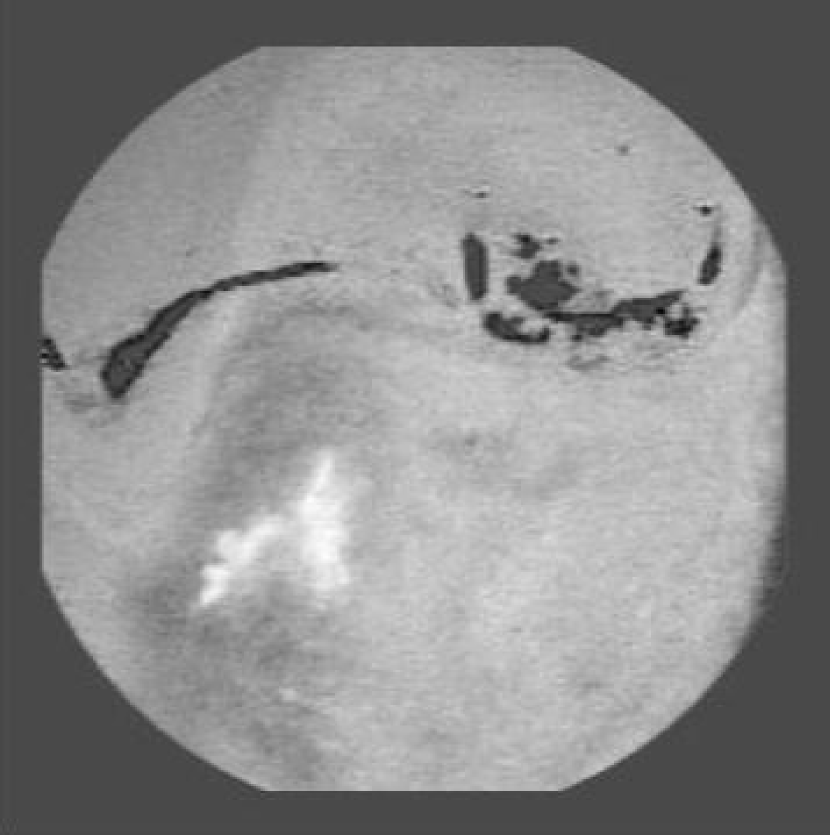

Refer to caption

(a) Original Image

(b) Annotation

(c) RoI selected of the ‘a’ component image

Figure 2: Selection of Region of Interest